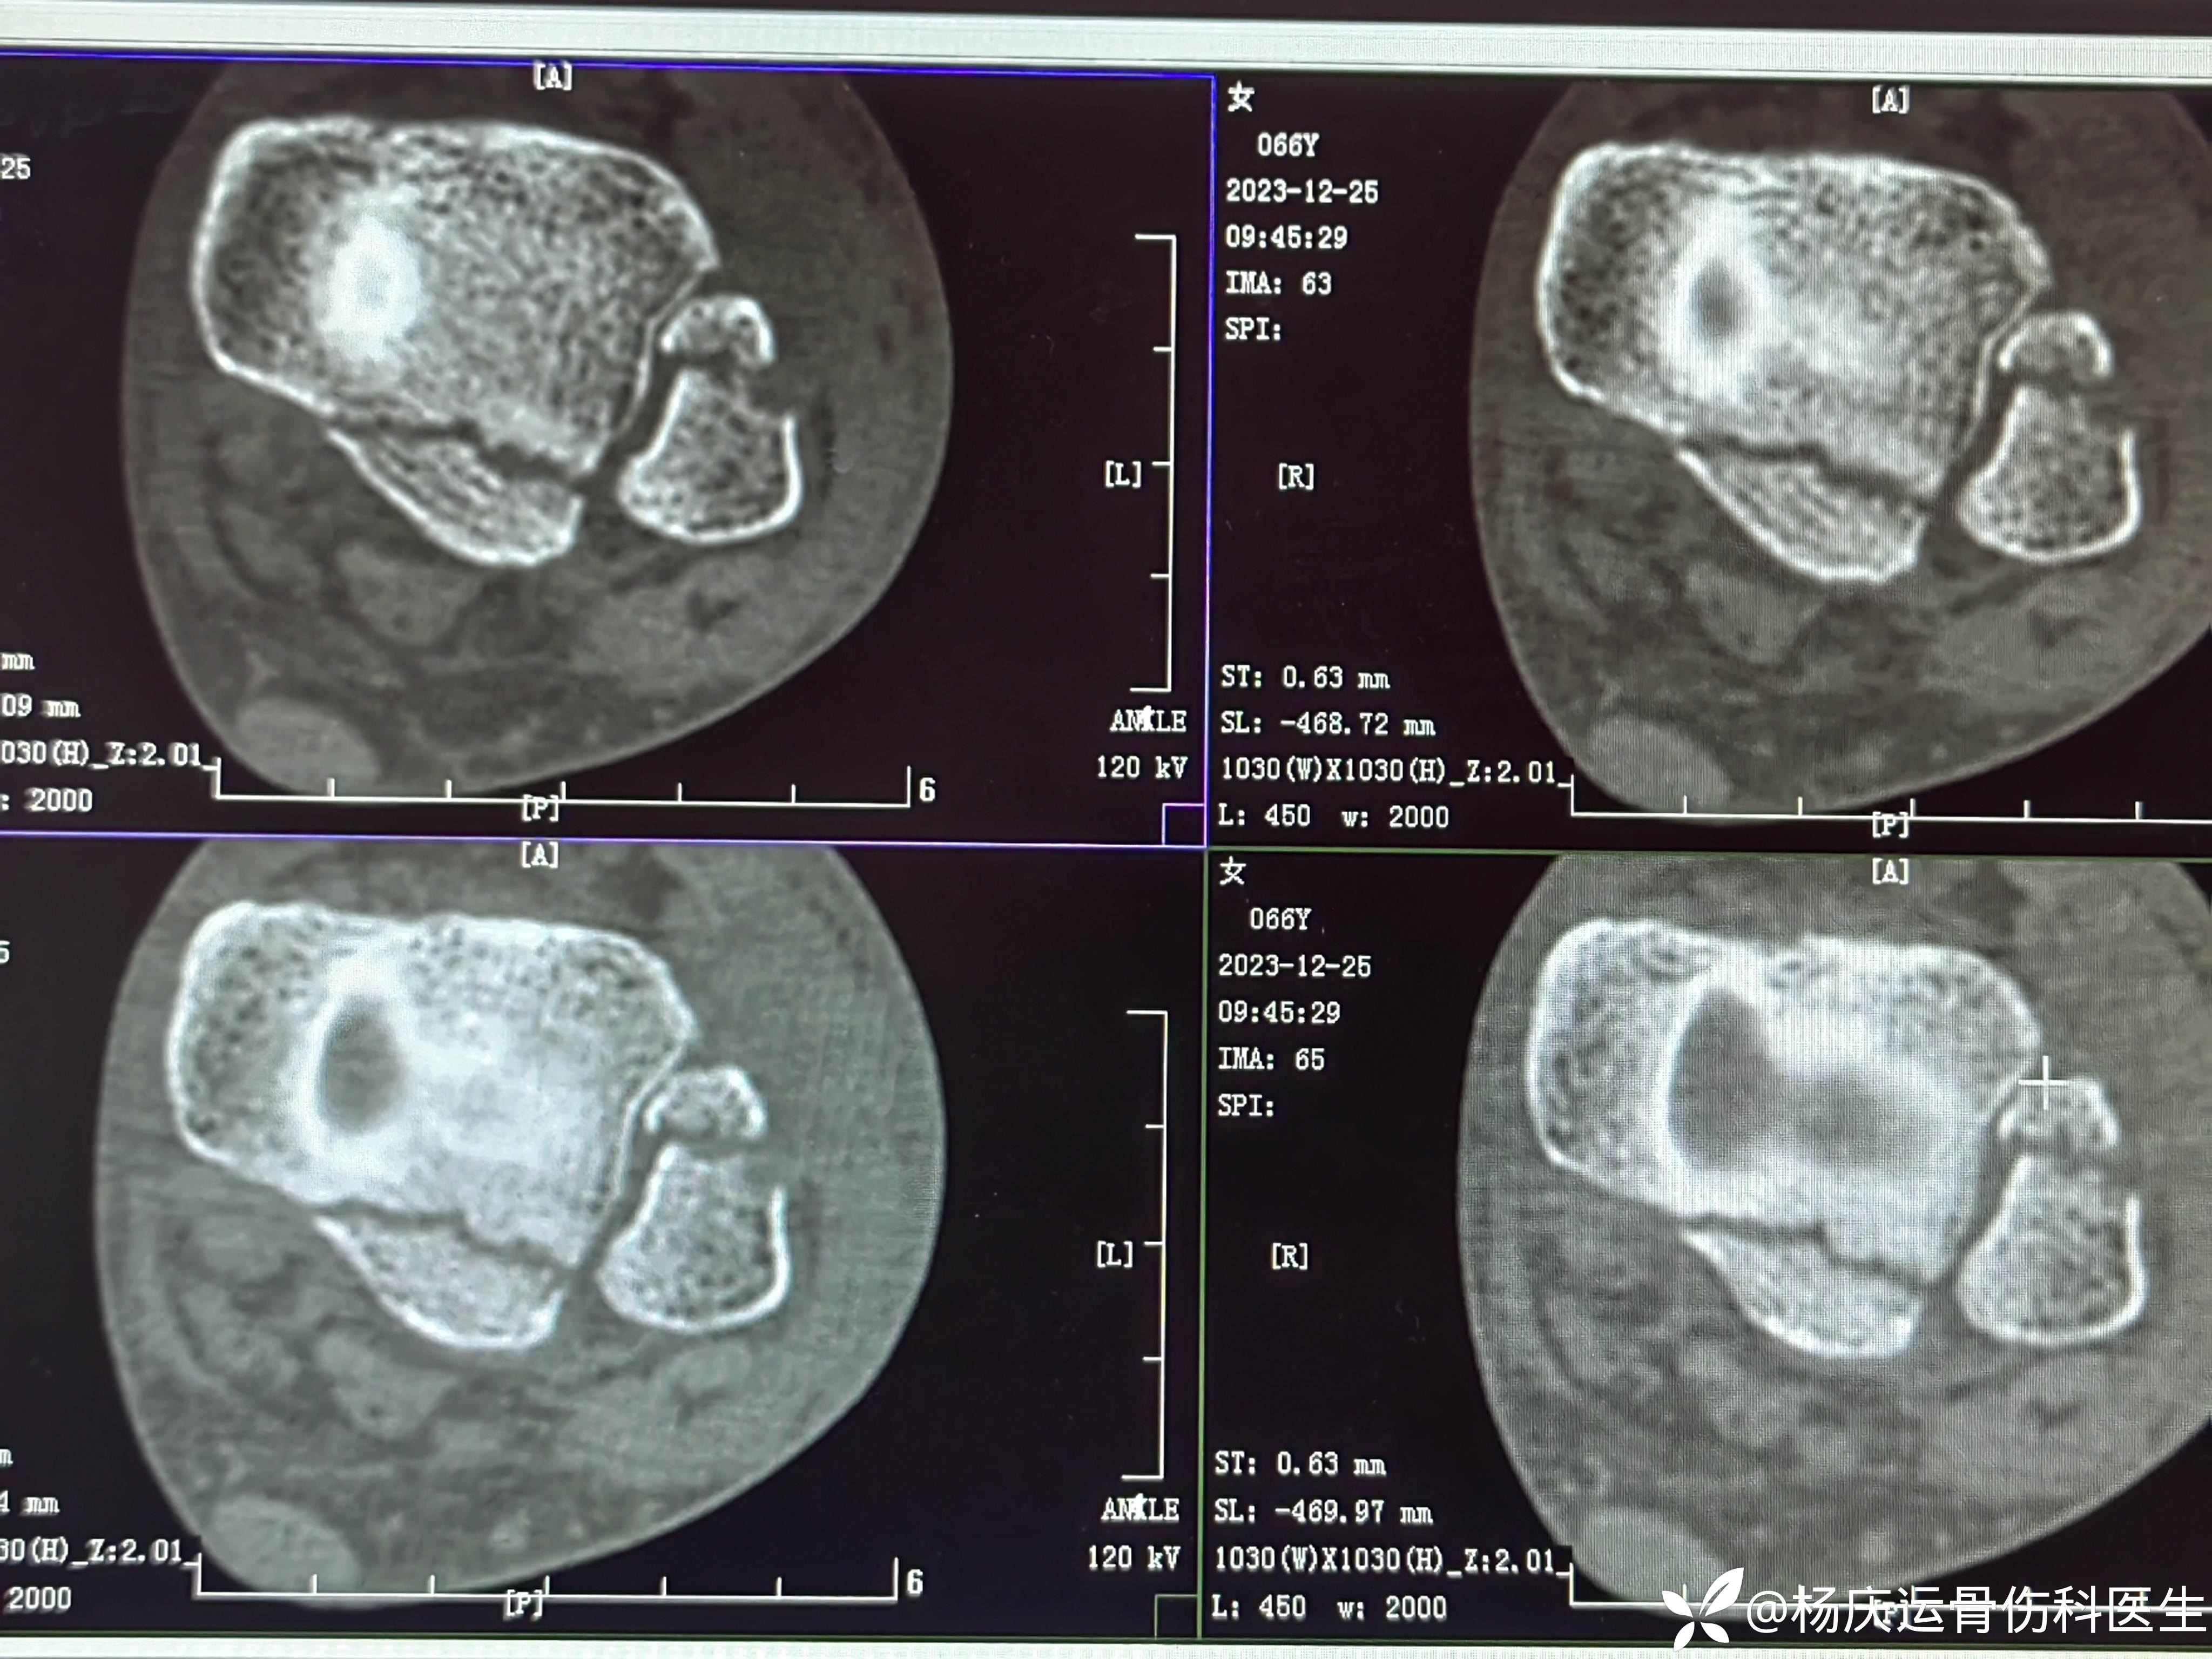

患者矫,女,66岁,左踝扭伤肿痛畸形2小时

初步诊断:左踝关节骨折(L-H分型:旋后外旋型IV)

CT

复位后